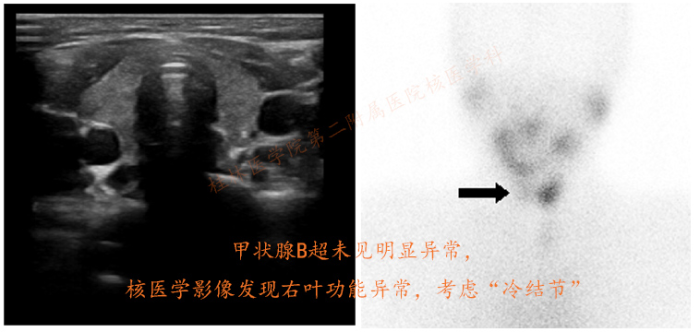

甲状腺癌的诊断通常通过症状、影像学发现,病理来明确的,其中甲状腺B超检查是首选,少数需要CT或核医学的甲状腺显像方法辅助来提高准确率。

核医学的甲状腺显像属于功能性影像检查,有别于传统的B超、CT、磁共振等。疾病的发生与发展过程中,往往早期是一些细胞或组织的功能性改变,随着这些功能异常的“累积”,最终大部分才在外形上体现。传统影像学是通过形态的改变来评估与诊断的,而核医学是通过组成形态内部的细胞组织的功能来判断是否异常,此时外观可能还没有改变,但内部功能发生了异常,这预示已经病变了。因此,核医学在某种程度上,有提前发现的作用,这也是核医学影像学检查的优势与特点。当然并不是所有的疾病都能预测的,因此CT、B超等检查仍是必要的,而结合功能性检查会提高准确性。

甲状腺B超正常,甲状腺核医学冷结节

↓   ↓   ↓